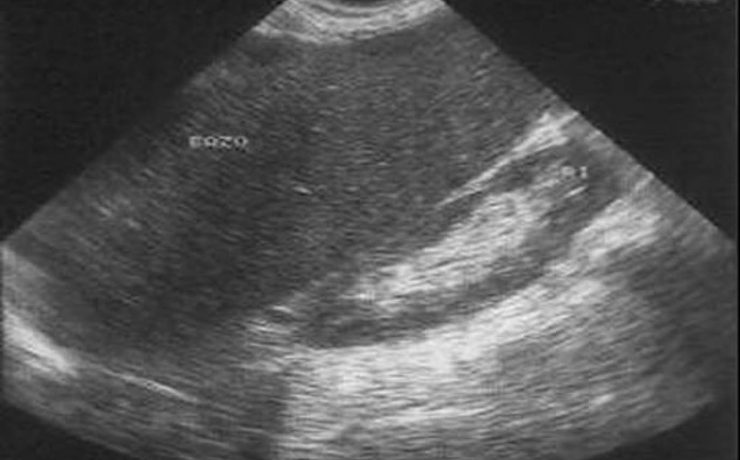

Anatomía y procesos fisiopatológicos principales del bazo.

El bazo en un órgano único macizo de consistencia blanda, en forma de esfera alargada, que se encuentra situado en abdomen superior, específicamente en el hipocondrio izquierdo, con peso variable de entre 80 y 300 gramos y con una longitud no mayor de 11 cm y distancia transversa de aproximadamente